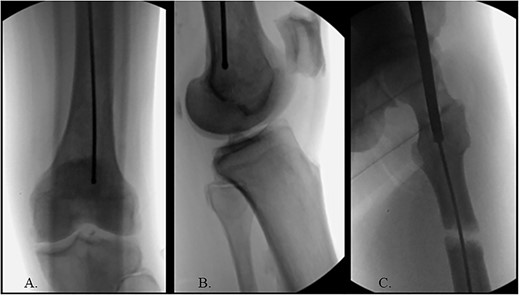

The patient was positioned supine on a fracture table. A guide wire was inserted through a 4-cm surgical incision proximal to the greater trochanter (GT) and was passed through a cannulated awl in a position slightly medial to the tip of the GT on the AP and center on the lateral (Fig. 2B). A (15-mm) entry reamer widened the opening (Fig. 2C). A rigid cannulated reduction rod and forceful malleting allowed the ball-tipped guidewire to cross the close reduced fracture, but too lateral and posterior distally (Fig. 3A and B). The cannulated flexible reamers encountered impassible blastic lesions within the proximal femur (Figs 3C and 5B).

(A) Ball-tipped guidewire slightly lateral position at the knee on the AP XR; (B) ball-tipped guidewire too posterior at the knee on the lateral XR; (C) flexible reamer within the proximal femur abutting blastic lesions.